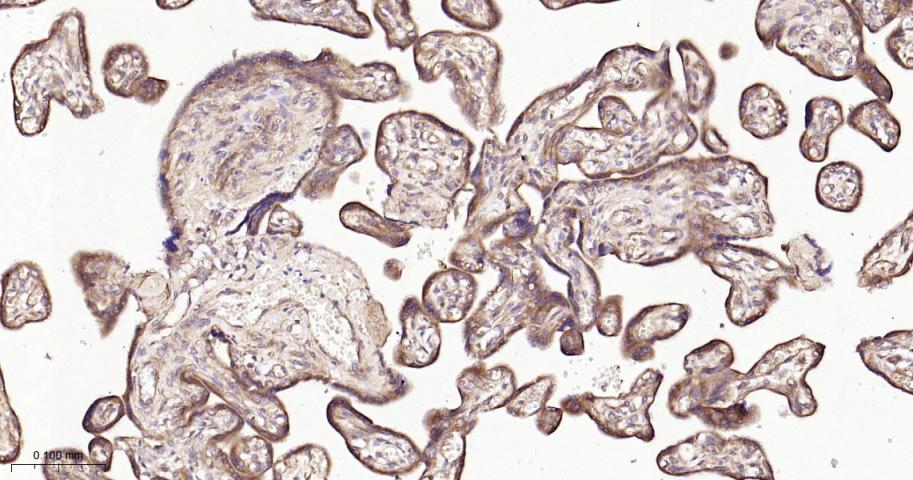

Paraformaldehyde-fixed, paraffin embedded Human Placenta; Antigen retrieval by boiling in sodium citrate buffer (pH6.0) for 15 min; The section was incubated with RACGAP1 Monoclonal Antibody, Unconjugated (bsm-62359R) at 1:200 overnight at 4°C, followed by conjugation to the bs-0295G-HRP and DAB (C-0010) staining.